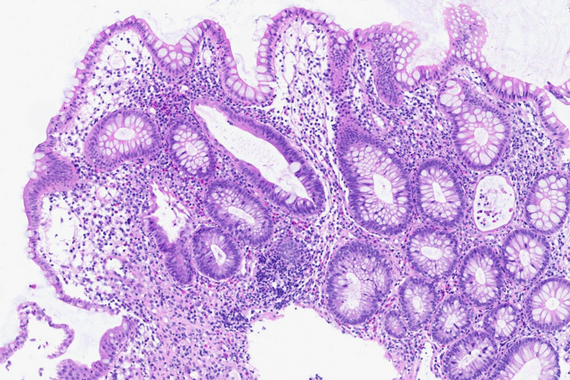

Ultrasound-guided biopsy of a pancreatic lesion in a 38-yeard-old woman (histological and cytological correlation).